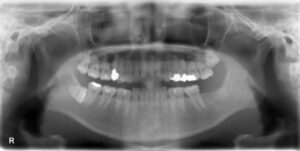

下顎大臼歯1本欠損症例

BEFORE AFTER 29歳女性/下1本欠損/インプラント埋込手術 【治療内容】 左下第二大臼歯の被せ物が土台ごと外…